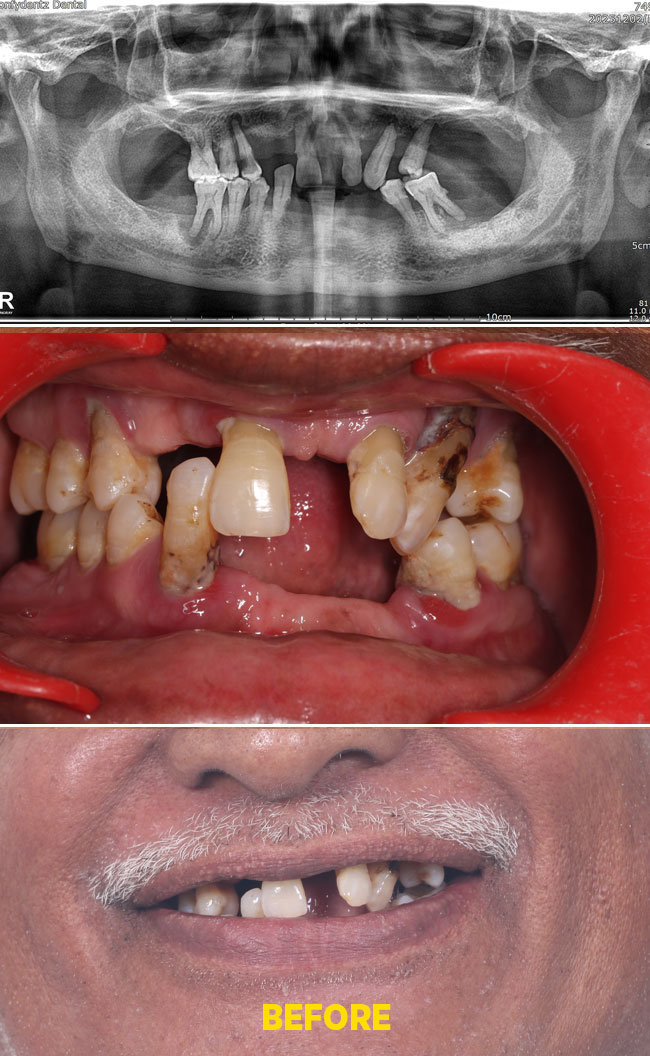

Case - 3